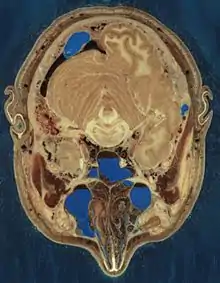

Le Visible Human Project vise à créer une base de données de photographies de sections du corps humain. Deux cadavres, celui d’un homme et celui d’une femme, ont été découpés en fines tranches, chacune de ces sections étant ensuite photographiée et numérisée[1]. Le projet est dirigé par la National Library of Medicine des États-Unis, sous la direction de Michael J. Ackerman. La conception du projet a débuté en 1986, la récolte des données relatives au corps humain masculin a été achevée en , et celle du corps féminin en . Le projet peut être observé au Musée National de la Santé et de la Médecine à Washington[2]. Il est envisagé de reprendre ce projet, avec des images de plus haute définition, mais seulement avec des parties du corps, au lieu d’un cadavre.

Le cadavre masculin a été plongé et gelé dans un mélange de gélatine et d’eau afin de le stabiliser pour la découpe. Le spécimen a été ensuite découpé dans le plan axial à des intervalles de 1 mm. Chacune des 1 871 tranches ainsi obtenues a été photographiée en analogique et en numérique, fournissant finalement 15 gigaoctets de données. Les images ont été renumérisées à l'an 2000 pour une meilleure résolution, produisant plus de 65 gigaoctets. Une version abrégée de 463 coupes en basse définition, reconstituée sur un axe similaire à celui d’un scanner (et non l’axe anatomique standard) a été créée en 2021 par un site d'imagerie médicale[3].

Les données ont été enrichies de sections axiales du corps entier, obtenues par tomodensitométrie (ou scanner), des sections axiales de la tête et du cou obtenues à l’aide d’une IRM et de sections frontales également obtenues par une IRM.